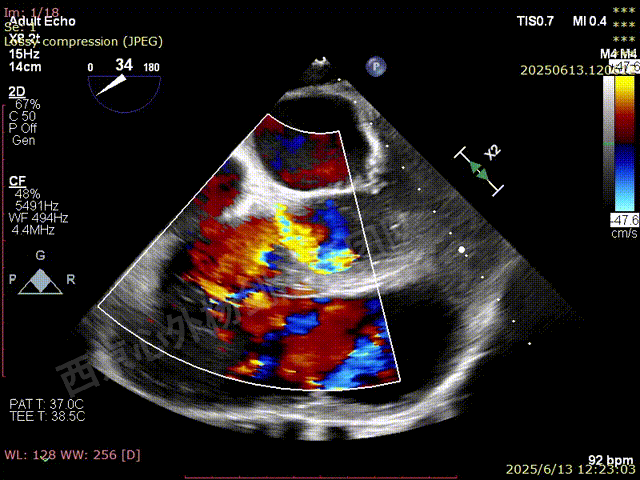

TAVR术后,全心增大,二尖瓣反流重度,三尖瓣反流重度。中量心包积液。左室严重增大,标准图像调整困难。主动脉瓣位带支架人工瓣膜瓣叶启闭正常,主动脉瓣位人工瓣上血流速度Vmax 148cm/s,PGmax 9mmHg,Vmean 86cm/s,PGmean 2mmHg, VTI 34.7cm,瓣周反流(轻)。估测肺动脉收缩压约49mmHg;左室收缩功能明显减低。LVEF:23%,EDV:364ml,ESV:221ml。

彩色血流示:二尖瓣反流缩流颈彩宽6.6mm,面积17cm²,容积30ml;二尖瓣瓣口面积6.6cm²,瓣环内径:左右径34mm,前后径34mm。2区瓣叶长度:前叶36mm,后叶20mm,叶环比1.6. 三尖反流面积17.2cm²,容积33ml,Vmax 291cm/s,PGmax 34mmHg。

二尖瓣后叶栓系严重,前叶相对错位,反流束沿2区分布广泛,2偏3区处存在反流。

反流宽度至少23mm,因影像调整困难,考虑实际反流更宽。